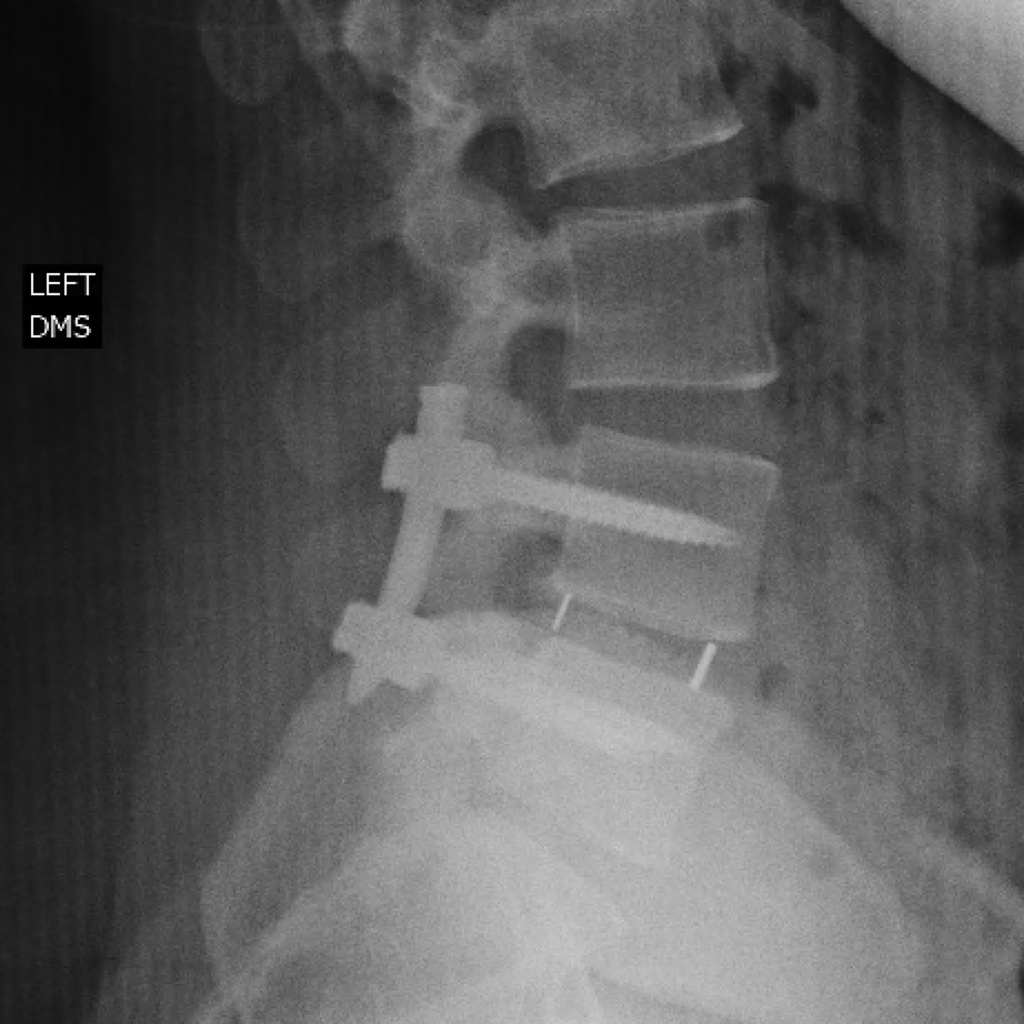

Spine-related injuries can be devastating, and it is important to seek opinion from an expert dedicated to total spine care. Dr. Bjerke is available to provide clinical expertise in the following areas: